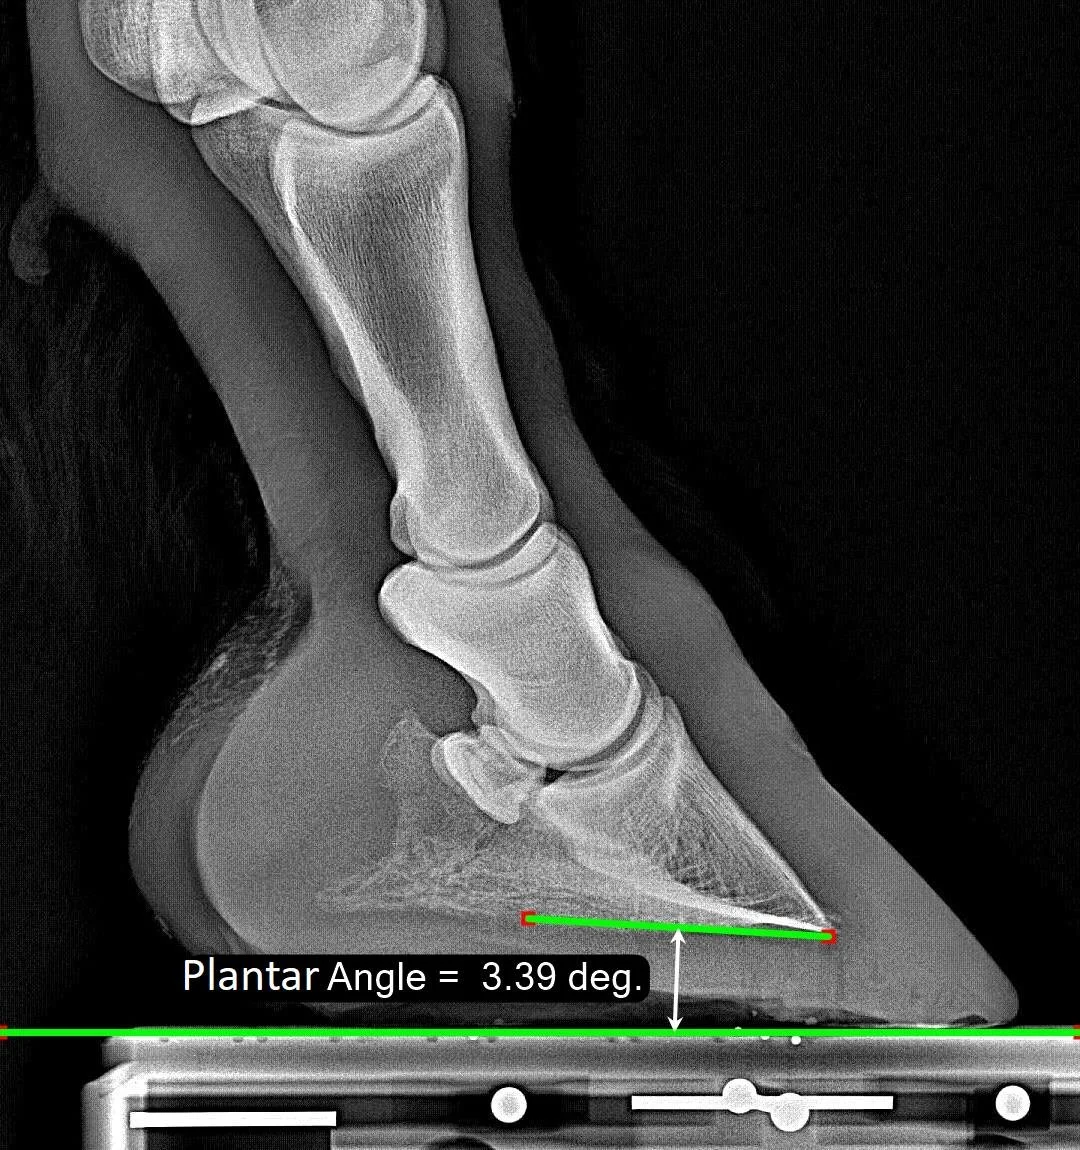

Plantar Angle

The Plantar Angle describes the shallow angle between the bottom of P3 and the ground. It grows more positive as the heels are raised. If the heels are very low, the Plantar Angle can become negative.

Normal Range

For a hind hoof, our ‘normal range’ is from -0.2 degrees up to 7.3 degrees, with the median at 3.7 degrees. The black vertical line shows the value for this image. Our reports also show the Plantar Angle on page 1 with the distribution colored by quartiles.